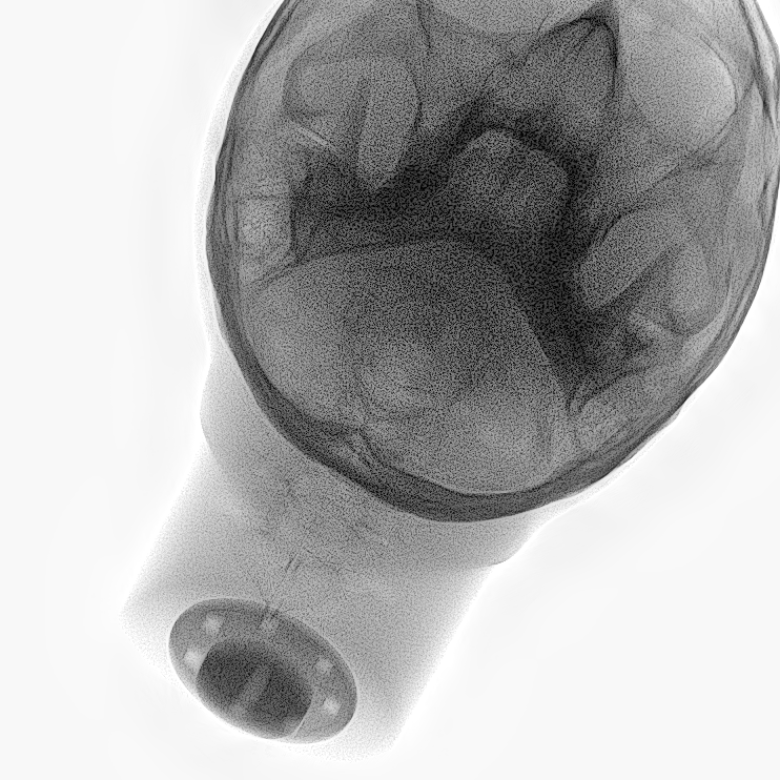

Refer to caption

Figure 2: Dataset overview. The synthetic domain contains Low and High dosage samples generated using the Mentice VIST® simulator; the real domain includes Low, Normal, and Exposure dosage categories acquired from a skull phantom using the Philips Azurion IGT system.

We develop and release a new dataset of real and synthetic head X-ray images, X-DigiSkull, to study the domain adaptation. The dataset consists of synthetic X-ray images of a human skull generated using the Mentice VIST® simulator 111https://www.mentice.com/simulator/vist-g7. Real‑time X‑rays are generated by holding the 3D voxel “patient” head model with per‑voxel attenuation, casting one ray per detector pixel to form a digitally reconstructed radiograph and then approximating scatter, focal‑spot and detector blur, grid/heel effects and detector response, adding quantum/read noise and final image post-processing as the C‑arm and devices move. Real images are acquired from a clinical-grade physical skull phantom using the Philips Azurion Image Guided Therapy (IGT) system. Images are captured from common IGT working positions for neuro procedures. The dataset consists of multiple orientations and is available in three different radiation dose settings: low, normal, and exposure (Philips exclusive), the latter offering enhanced image quality and detail, as shown in Figure 2. This consists of viewing angles rz[40,+40]r_{z}\in[-40^{\circ},+40^{\circ}], ry[40,+40]r_{y}\in[-40^{\circ},+40^{\circ}], rx[40,+40]r_{x}\in[-40^{\circ},+40^{\circ}] with respect to the starting position in 10 increments and up to 3 images at each position to capture the noise present. This results in a total of 2,187 real images. The coordinate systems of the real and synthetic environment are aligned and synthetic images are rendered to approximate the same viewpoints as the real phantom images with the patient table starting at a similar position.The head 3D model used in the simulation is meticulously built from a real clinical case. We capture the synthetic images in finer increments of 5 across the three angles, producing the 5,832 (18318^{3}) images 222Data available at https://zenodo.org/records/16535437. The aim of this alignment is not to achieve precise supervised image translation, but rather to establish a consistent reference structure that preserves spatial features. The composition of the dataset is summarized in Table 1, which contains information on the splits and the number of images available. All images are cropped and resized to 780×\times780 pixels. The test set is obtained by uniformly sampling 15% of viewing angles and corresponding images to ensure a representative distribution. For our experiments, we focus on the task of converting synthetic images at high dose to real images at normal dose.